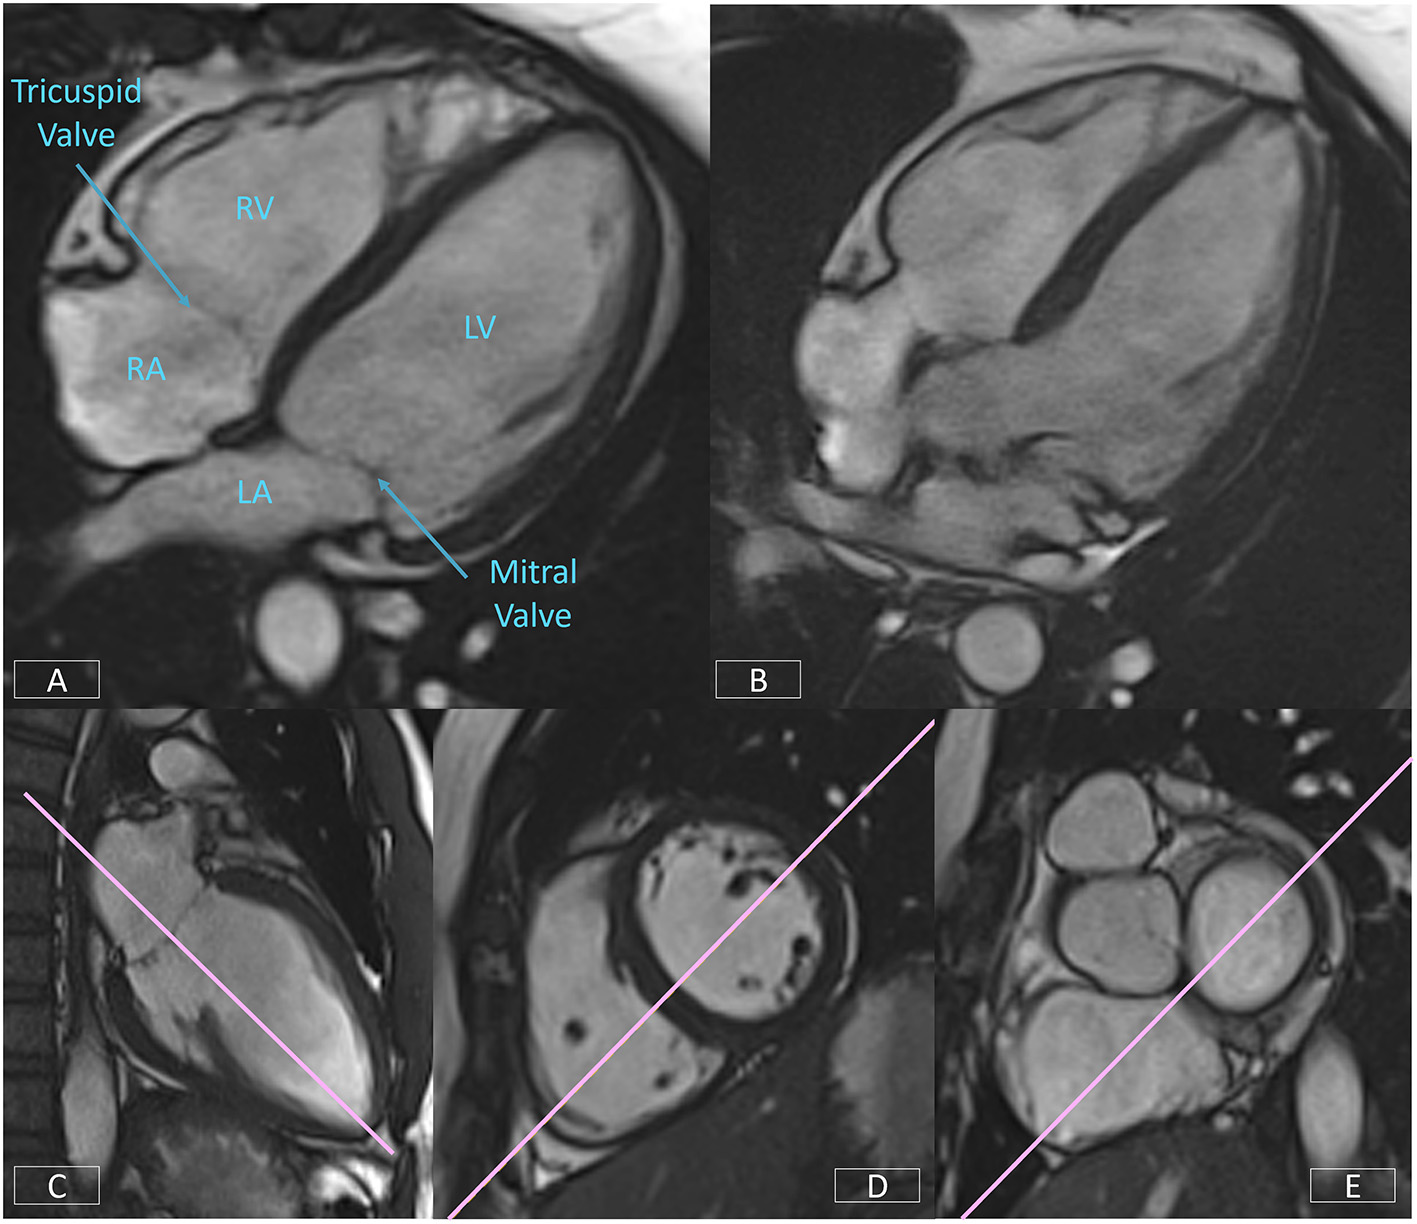

The 4-Chamber View

The 4-chamber view affords an overall visual assessment of cardiac function. A well-positioned view (Figure 8A) will demonstrate the mitral and tricuspid valves and the right and left atria and ventricles. However, frequently the four cardiac chambers and the atrio-ventricular valve planes are not well-visualized due the slice plane being prescribed incorrectly. Figure 8B is an example of a poorly positioned 4-chamber with the slice plane prescribed through the LV OT. To successfully position the 4-chamber view requires the use of three views. On the LV VLA view (Figure 8C), the operator should ensure the slice plane is prescribed through the center of the mitral valve and the LV apex. On a mid-ventricular LV SAX slice (Figure 8D), the plane is tilted down to the RV apex. Finally, the position is cross-checked on a basal LV SAX view (Figure 8E) to ensure the slice positioning avoids the LV OT and aortic root.

Figure 8

Well-positioned 4-chamber view (A) demonstrating mitral and tricuspid valves, right and left atria, and ventricles. Incorrect prescription (B) with the slice plane prescribed through the LV OT. Accurate positioning of the 4-chamber view requires the use of three views, the LV VLA view (C), mid-ventricular LV SAX slice (D), and the basal LV SAX slice (E).